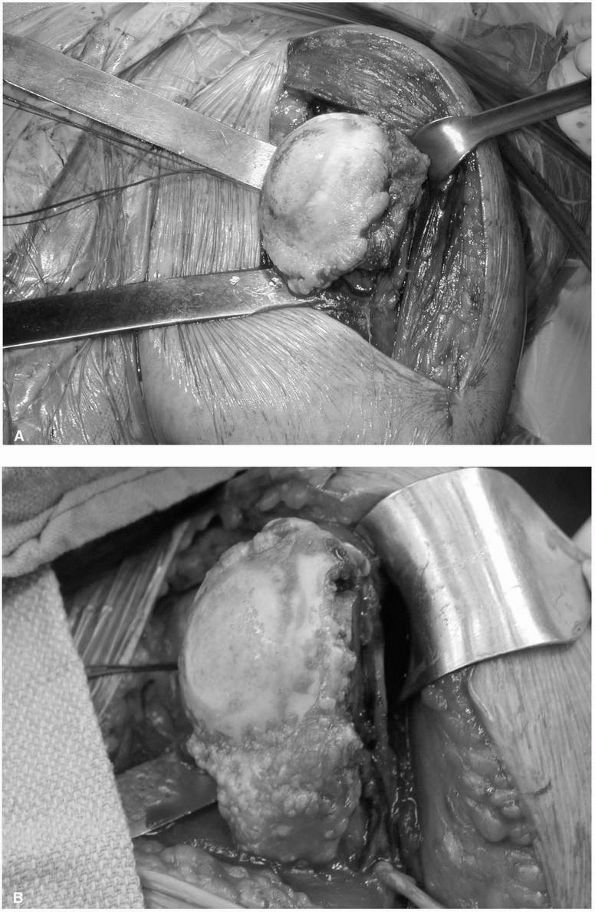

![]() |

FIGURE 12-6. (A) and (B)

Intraoperative photographs of glenohumeral arthritis with flattening of the head, loss of articular cartilage, eburnation of the subchondral bone, and large peripheral osteophytes. |